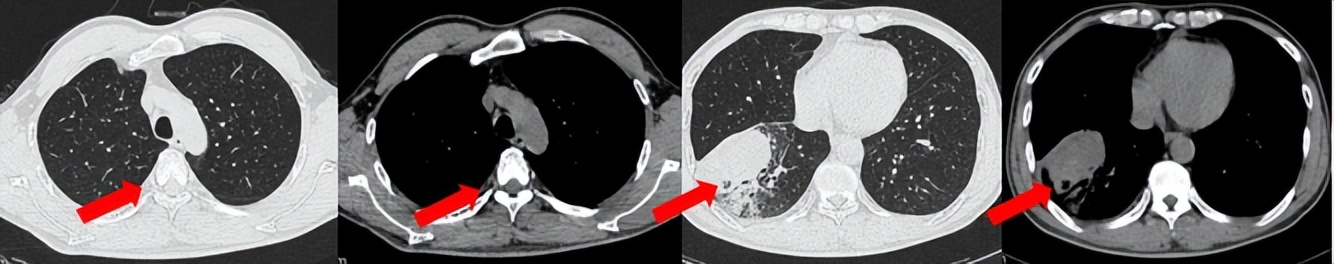

53岁男性,无吸烟饮酒史,脑血栓病史。2024年7月胸部CT:右肺下叶见一团块状软组织密度影,范围约10.8×9.0cm,边界不清,周围并见斑片状磨玻璃密度影,右肺下叶前底段支气管阻塞。纵隔及右肺门见肿大淋巴结影。考虑右肺下叶支气管肺癌。伴纵隔及右肺门淋巴结转移瘤,右下肺静脉瘤栓。2024.7.23行肺穿刺取病理:(肺)腺癌伴有神经内分泌分化。NGS基因检测:RET KIF5B exon15-RET exon12融合。PD-L1(克隆号28-8)TPS=90%。

治疗经过:2024.08开始口服赛普替尼(160mg,bid)。2024.09复查胸CT评效PR。2025.1复查胸CT:右肺下叶外基底段见一不规则形实性肿块,大小约94mm×87mm,边缘呈分叶状,其内密度不匀。右侧胸腔见少许水样密度影。评效PD,PFS=5个月。患者未同意再次组织活检,目前应用卡博替尼治疗,仍在随访中。治疗期间未出现毒性反应。

2024.08

2024.09评效PR

2025.01评效PD